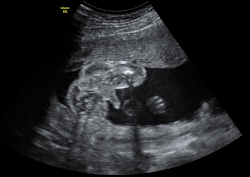

En la semana 20 de gestación el feto aún tiene mucho espacio para poder moverse. La embarazada notará esos movimientos, que se observan en la ecografía en 4D. Son las clásicas "pataditas" que nota la madre dentro del útero.